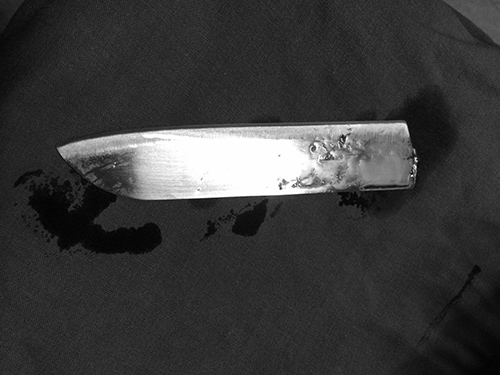

10月27日晚上9时许,省人民医院急诊科的电话突然响起,120紧急转入一名年轻病人,病人由朋友陪护到医院,鲜血染湿了他的上衣。只见他的左胸还在不断渗血,摄片显示惊人的一幕:一柄狭长的刀刃刺入了他的胸腔,10—12cm刀刃完全留置在左侧胸腔,刀柄已经断裂。

接到这名危急病人,我院打开急诊绿色通道,入院后立刻转至手术室,5分钟后心胸外科专家紧急会诊,决定马上进行手术,取出胸腔刀具,抢救病人生命。此时病人胸腔几乎都是积血,呼吸衰弱,血压下降。麻醉师周涛迅速为病人麻醉气管插管,主刀医师、心胸外科主任医师柳阳春果敢的带领主治医师林庆果敢、快速的开胸,只见刀刃贯穿左上肺、左下肺,刺破肺血管,割断背段支气管。柳阳春介绍,刀刃卡在两根肋骨之间,深深的切进肋骨中才没有进一步刺入,“如果再进一点,伤及胸主动脉,病人必定当场死亡。”

手术中进行了左侧血气胸清除、肋间血管缝扎、上下肺叶部分切除、肺血管缝扎、刀具取出、左下肺支气管缝扎,直至凌晨3点半才结束,成功取出刀具。